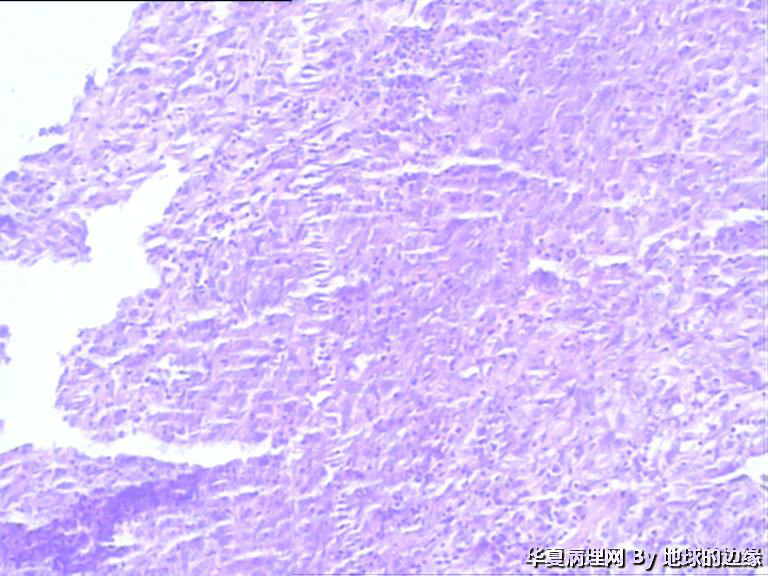

病人女性,48岁

MRI示:右肱骨肿瘤待排,包块大小为10x8cm,活动度差,边界欠清,鱼肉组织(白色),肿块侵犯至骨外    组  织。

目前Vimentin阳性,P53阳性,AFP,EMA,CK7,CK20,E-ca,CR,PLAP,CD99,ER,PR,CEA,均阴性,只是没做淋巴瘤这一套了

恶性。是转移还是原发,是骨肉瘤还是浆母?需要进一步资料并标记。

考虑肉瘤,转移癌也排除一下吧